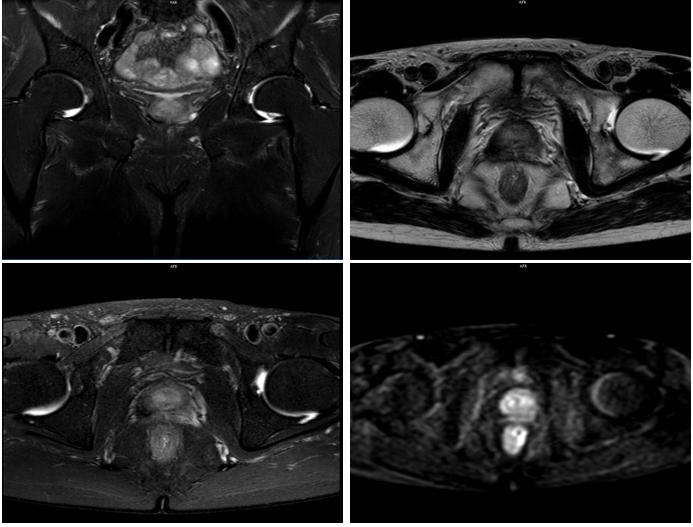

2020年5月12日,复查前列腺MRI+DWI示:前列腺信号欠均,DWI信号略高,外周带及中央带分界不清,盆腔未见明显肿大淋巴结。双侧精囊腺萎缩信号欠均。右侧耻骨联合见斑片状SPAIR高信号。

图4 患者起始醋酸阿比特龙治疗时,复查前列腺MRI+DWI状况